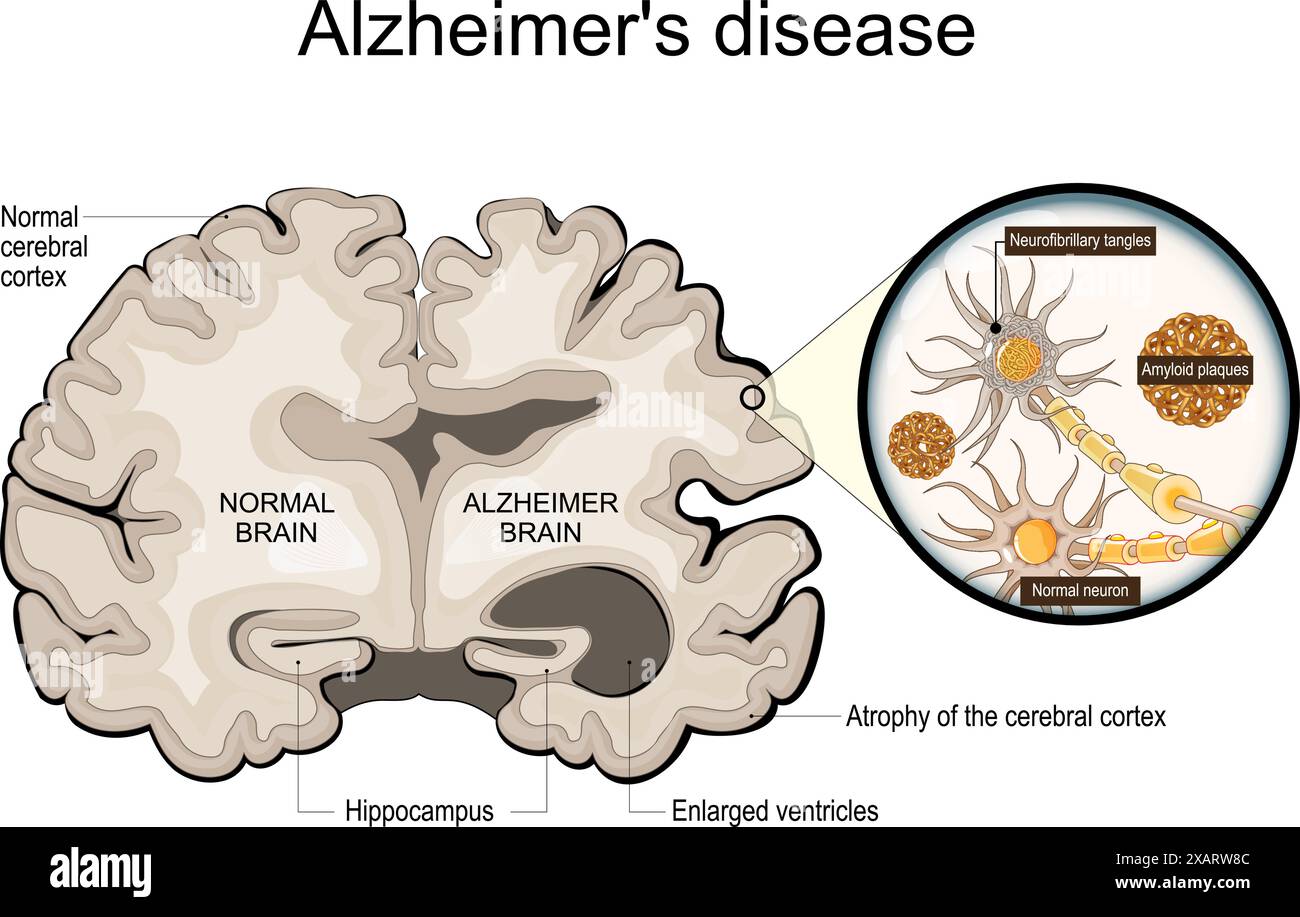

RF2XARW8C–Morbo di Alzheimer. Neurodegenerazione. Sezione trasversale del cervello normale e Alzheimer, con atrofia della corteccia cerebrale, ventricoli ingrossati e Hipp